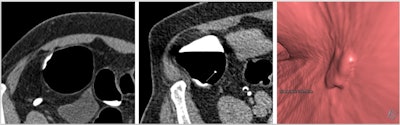

CT colonography (CTC) is a highly sensitive, well-tolerated test for the diagnosis of colorectal cancer and polyps, they explained. Colorectal cancer is the fourth most common cancer in the U.K., with over 42,300 cases a year. Currently, more than 100,000 CTC examinations are conducted each year in England alone, and this figure is increasing each year.

When performed to the highest quality, CTC has excellent diagnostic accuracy for clinically significant neoplasia -- i.e., colorectal cancer and advanced neoplasia -- in both symptomatic and screening populations. But unlike colonoscopy, substantial variations in practice exist in the U.K. and internationally, they added.